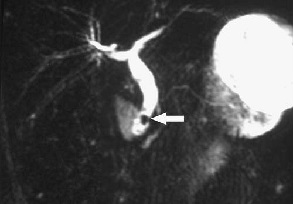

Clinical Preoperative Imaging

– 肝内胆管扩张 intra extra-hepatic bile duct dilation

– 肝外胆管扩张 extra-hepatic bile duct dilation

– 胆管阻塞的原因 cause/level of the obstruction

– 肝门部肿瘤 hilar tumor

– i肝内转移性扩散 ntrahepatic metastatic dissemination

– 腹水的程度 ascites level